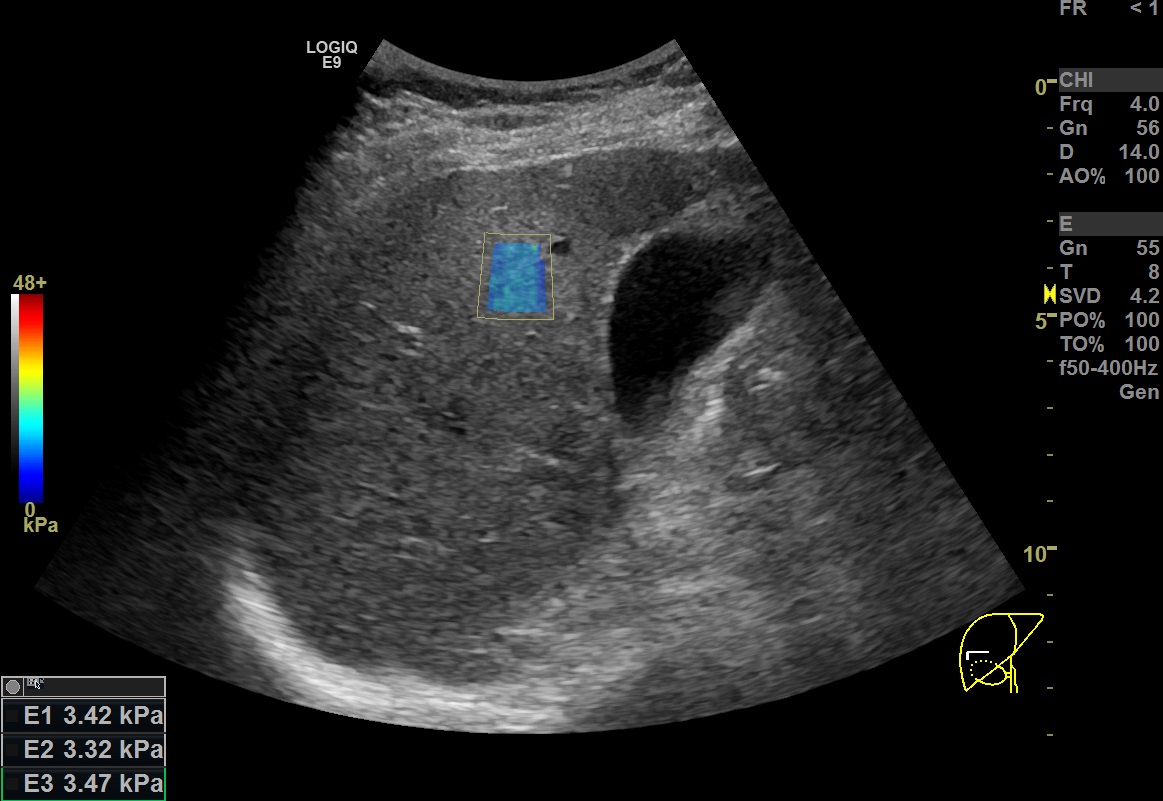

두번째로 생각해볼 점은 거사의 신뢰성을 판단할 때 사분위간 범위를 나누는 것보다 더 직관적인 방법으로서 2D SWE 시행 시 관심영역 내에 색으로 표시되는 부분이 얼마나 균일한 색상으로 고르게 분포되어있는가를 확인하는게 좋은 지표가 될 수 있다는 점입니다. 경험적으로 관심영역 내 색상이 균일한 경우는 여러번 측정했을 때의 측정값 또한 일정하게 편차가 적었습니다(위의 영상 참조).

이러한 경향은 정상환자에서나 간섬유화 등으로 stiffness가 증가한 환자에서나 공히 보이는 경향이었습니다.

2D SWE를 시행하는 동안에는 이렇게 관심영역의 색상균일도를 확인하면서 한 번 측정할 때마다 제대로 측정한 유효검사인지를 쉽게 체크할 수 있었습니다.